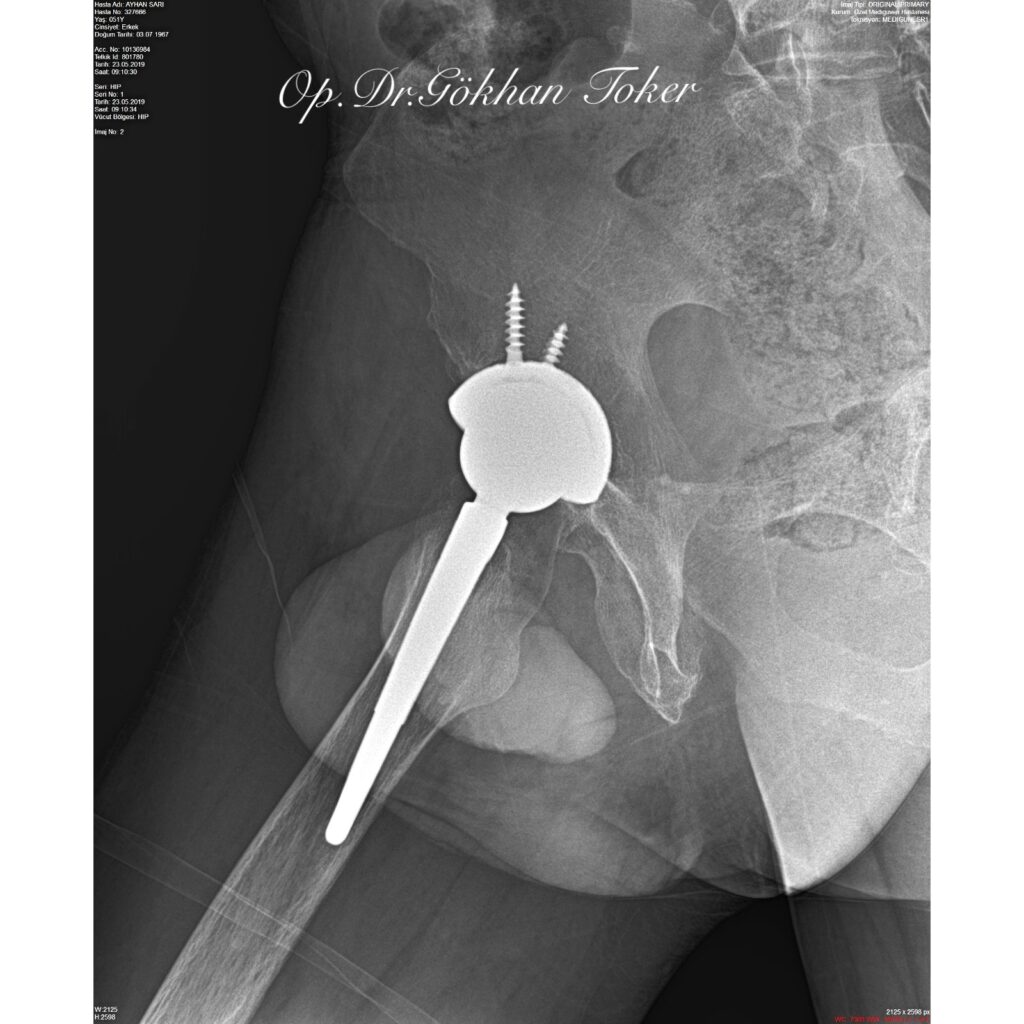

C.E.